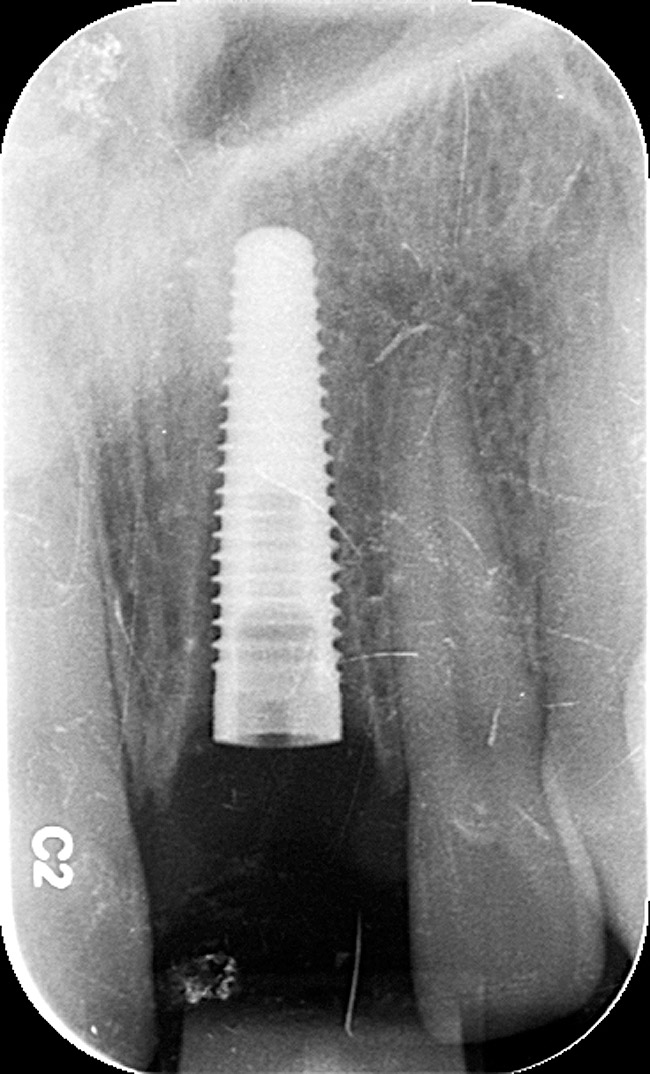

Figure 10  Tooth No. 9, pretreatment, showing Ellis Class III crown fracture; completed endodontic treatment, provisional post and core—periapical views.

Figure 10

Emergency endodontic treatment had been completed to manage the traumatically exposed root canal; Figure 10 shows the pre-treatment (Ellis Class III crown fracture) and post–endodontic-treatment periapical views of tooth No. 9. The restorative dentist temporarily cemented a glass-reinforced fiber post and used a fiber-reinforced composite core buildup material as an immediate provisional. Several weeks later, a provisional bis-acryl temporary crown on No. 9 was cemented on a larger-diameter glass-reinforced fiber post retaining a new fiber-reinforced composite core. Figure 11 shows the final feldspathic porcelain crown placed by the restorative dentist. During the fabrication and cementation of this crown, the remaining root appeared intact and the tooth was asymptomatic.